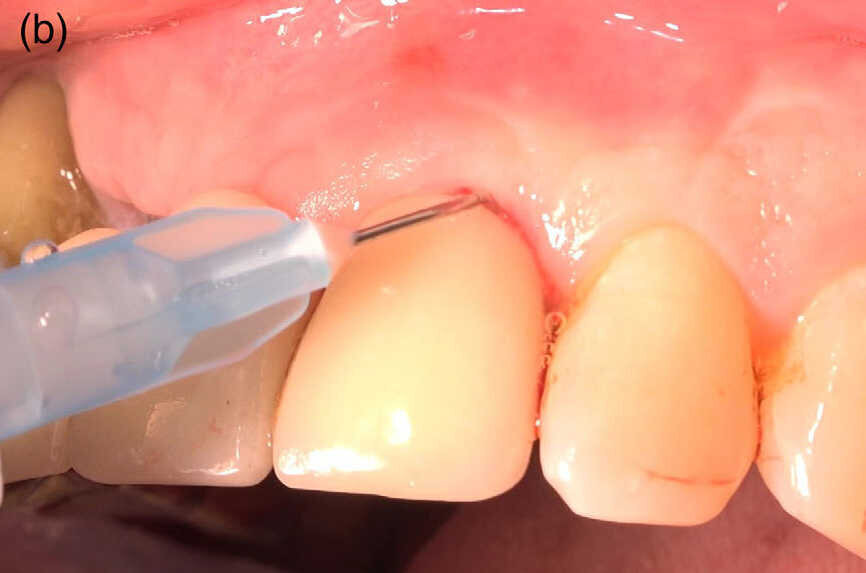

Fig 1 (b) : Injection d’hypochlorite de sodium à 0,95 % dans le sillon gingivo-dentaire, attente de 30 secondes pour un ramollissement du tissu de granulation et sa préparation pour une dégranulation par une curette.